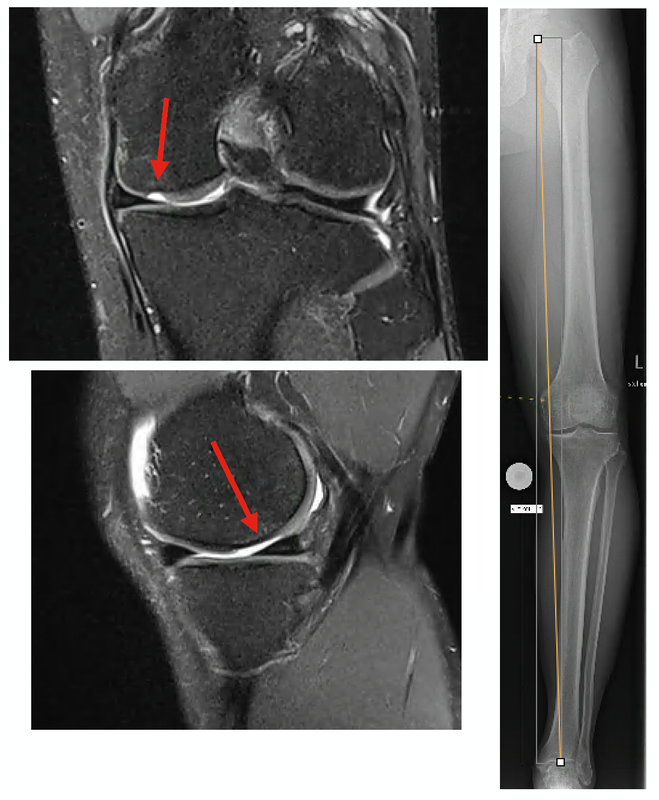

Defined, deep-seated cartilage defects should be treated with various cartilage restoration procedures. Also for these cartilage repair techniques the key for successful treatment is the as-sessment of the load-bearing axis of the leg. If there is malalignment causing stress for the defect this must be corrected before or during the cartilage restoration surgery (Fig 1).

Radiographic analysis requires a weight-bearing full leg and lateral knee joint x-ray and a standard axial image of the patella. In addition, the extent of the narrowing of the joint space in the affected joint compartment should be assessed with a Rosenberg view (p.a. radiograph with weight-bearing and 45 degrees of flexion) or stress x-rays with varus/valgus stress. Since large numbers of unicondylar knee replacements are performed in our hospital, stress radiographs are standard for any unicompartmental OA requiring surgical treatment. The extent of the joint collapse and the stability of the joint can be diagnosed by these radiographs (Fig. 6, 7).